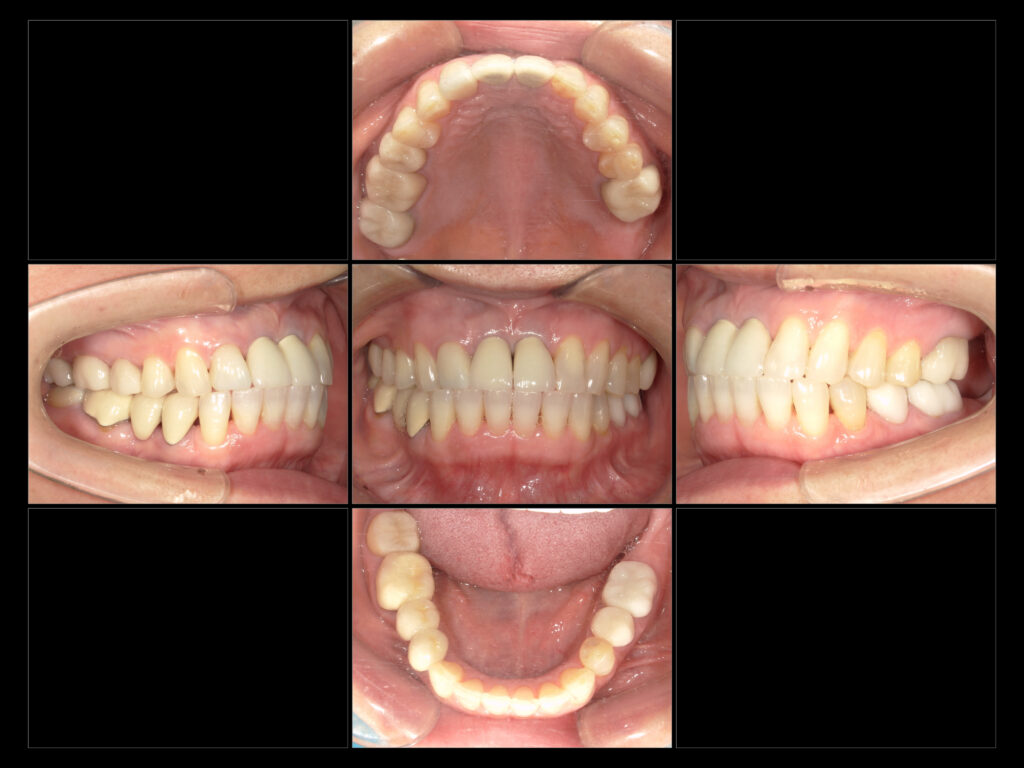

↑補綴終了時口腔内写真

右上567:emaxcr

左上5:emaxIn

左上6:emaxcr

左上2:emaxcr +イージーカラー

左下56:emaxcr

右下7:emaxcr

ホワイトニング

ボトックス

セラミックで自然な色味とバランスに整えました!

噛み合わせや見た目等細かく調整しています!